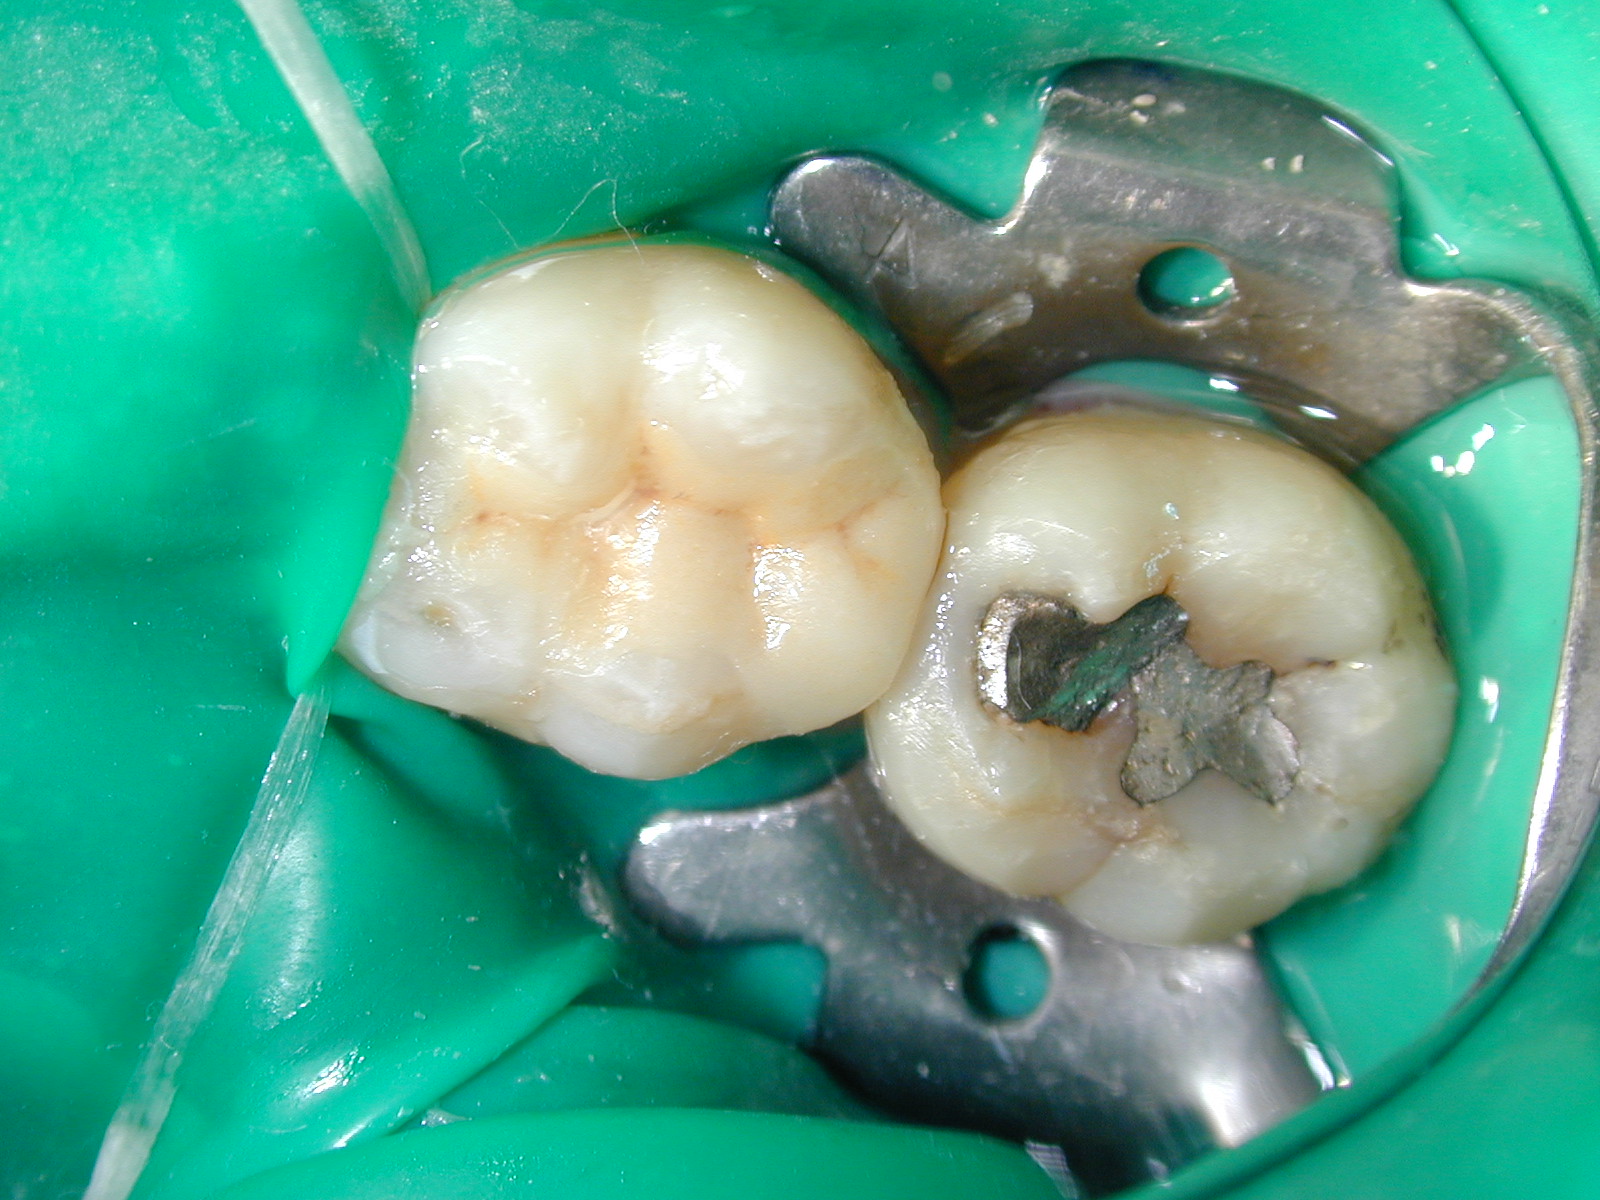

美容鑄造性瓷牙嵌體 取代傳統銀粉充填的齒色修復材

一般後牙有蛀牙時,通常用銀汞合金(俗稱銀粉)來修補牙齒,雖然它有高強度操作方便且費用便宜的優點,但由於和牙齒接合的地方,久了之後會有空隙產生,容易造成二度蛀牙,有時還會使牙齒變色,重要的是當蛀牙範圍很大時,銀汞合金的強度,並不適合用做修復材,而需以更強的嵌體或牙冠,來修補牙齒。

鑄造瓷牙嵌體的發展,在於彌補銀粉美觀上的不足,又同時能承受較大咬合力,更重要的是它的物理性質和牙釉質相近,使得它和牙齒的相容性很高。加上樹脂黏合劑的結合,幾乎可達到無接縫無空隙的理想效果。

取相同的模型鑄造一個瓷牙嵌體

放入模型

放入牙齒

用樹脂黏合劑結合傳統銀粉